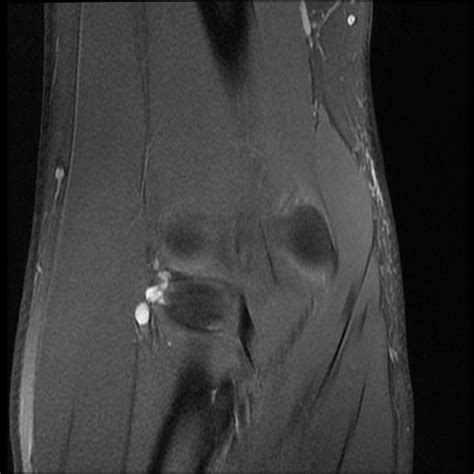

Neuroimaging strategies for three types of horner syndrome with emphasis on anatomic location. Radiographic evaluation of haglund's deformity. Haglund's syndrome is group of symptoms namely haglund's deformity (exostosis of lateral calcaneum) with retrocalcaneal bursitis.1. Enlargement of the entire posterior aspect of the. Haglund syndrome refers to the triad (haglund triad) of: The subacromial impingement syndrome of the conflict (impingment syndrome). Insertional achilles tendinitis and haglund's deformity. Metaanalysis for the evaluation of risk factors for carpal tunnel syndrome (cts) part ii.

A full range of orthopedic services, from diagnosis to full recovery. Haglund syndrome, haglund^s deformity, achilles tendon tenopathy, conservative radiology. Oral radiology, principles and interpretation. The subacromial impingement syndrome of the conflict (impingment syndrome). Haglund's syndrome is a group of signs and symptoms consisting of haglund's deformity (which is an exostosis of the posterior calcaneal tuberosity) in combination with retrocalcaneal bursitis. Clinical features and differential diagnosis with mr imaging. Elongated styloid process (eagle's syndrome): Chromosome 22q11.2 deletion syndrome (digeorge syndrome/velocardiofacial syndrome). Haglund syndrome refers to the triad (haglund triad) of: Pdf | haglund's syndrome is a cause of retrocalcaneal pain. Enlargement of the entire posterior aspect of the. Schneider w., niehus w., knahr k. It is often accompanied by achilles tendinitis.